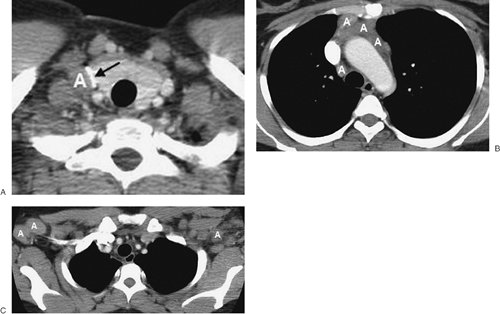

FIGURE 6-22. Hodgkin lymphoma. A: CT scan shows right supraclavicular lymphadenopathy (A) compressing the right jugular vein (arrow). B: CT scan at a more inferior level shows confluent anterior mediastinal and right paratracheal lymphadenopathy (A). C: Another CT scan shows bilateral axillary lymphadenopathy (A).